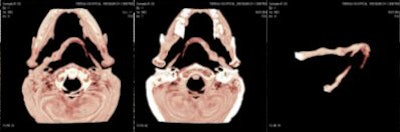

CT scan showed the presence of ossification of the right stylohyoid chain articulating with the hyoid bone. An elongated styloid process was present on the left side.